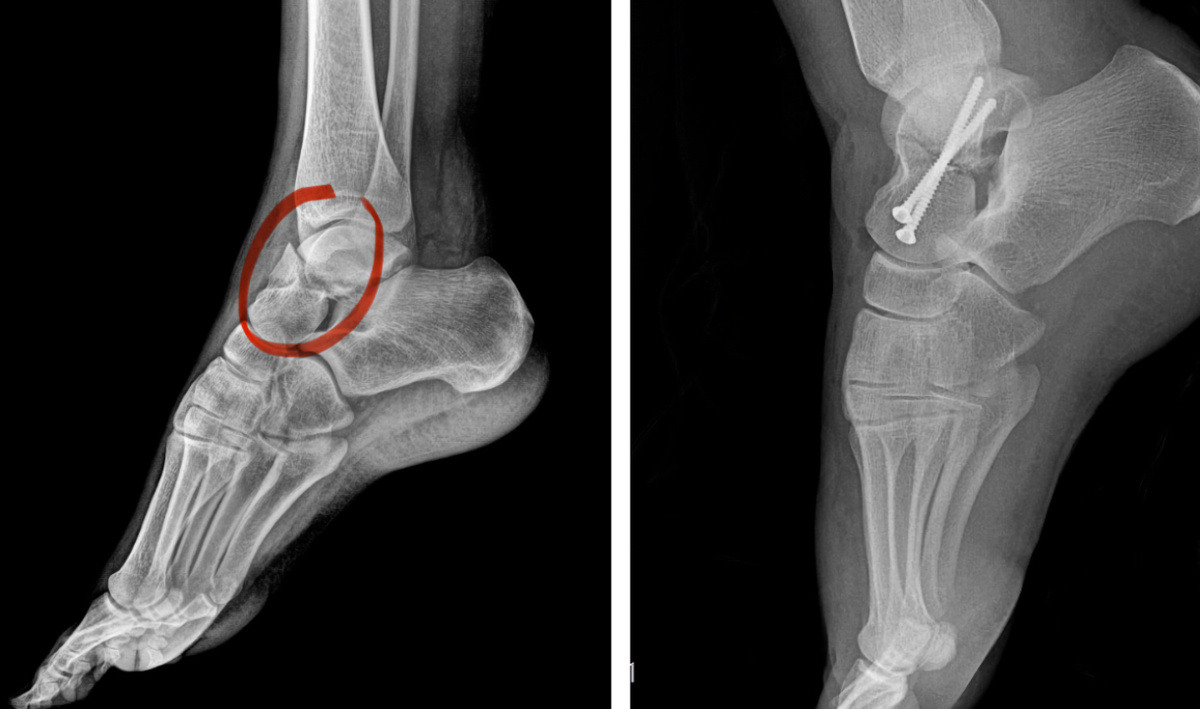

До и после.

В больнице №2 девушке восстановили стопу после падения с лошади

После травмы на тренировке у девушки выявили сложный перелом таранной кости со смещением. Врачи решили действовать быстро — и провели артроскопическую операцию. Такой метод требует лишь проколов и позволяет точно сопоставить отломки.

Операцию выполнили Олег Ипполитов и Евгений Козюбенко. Через 4 дня пациентку уже выписали — она продолжает лечение амбулаторно.